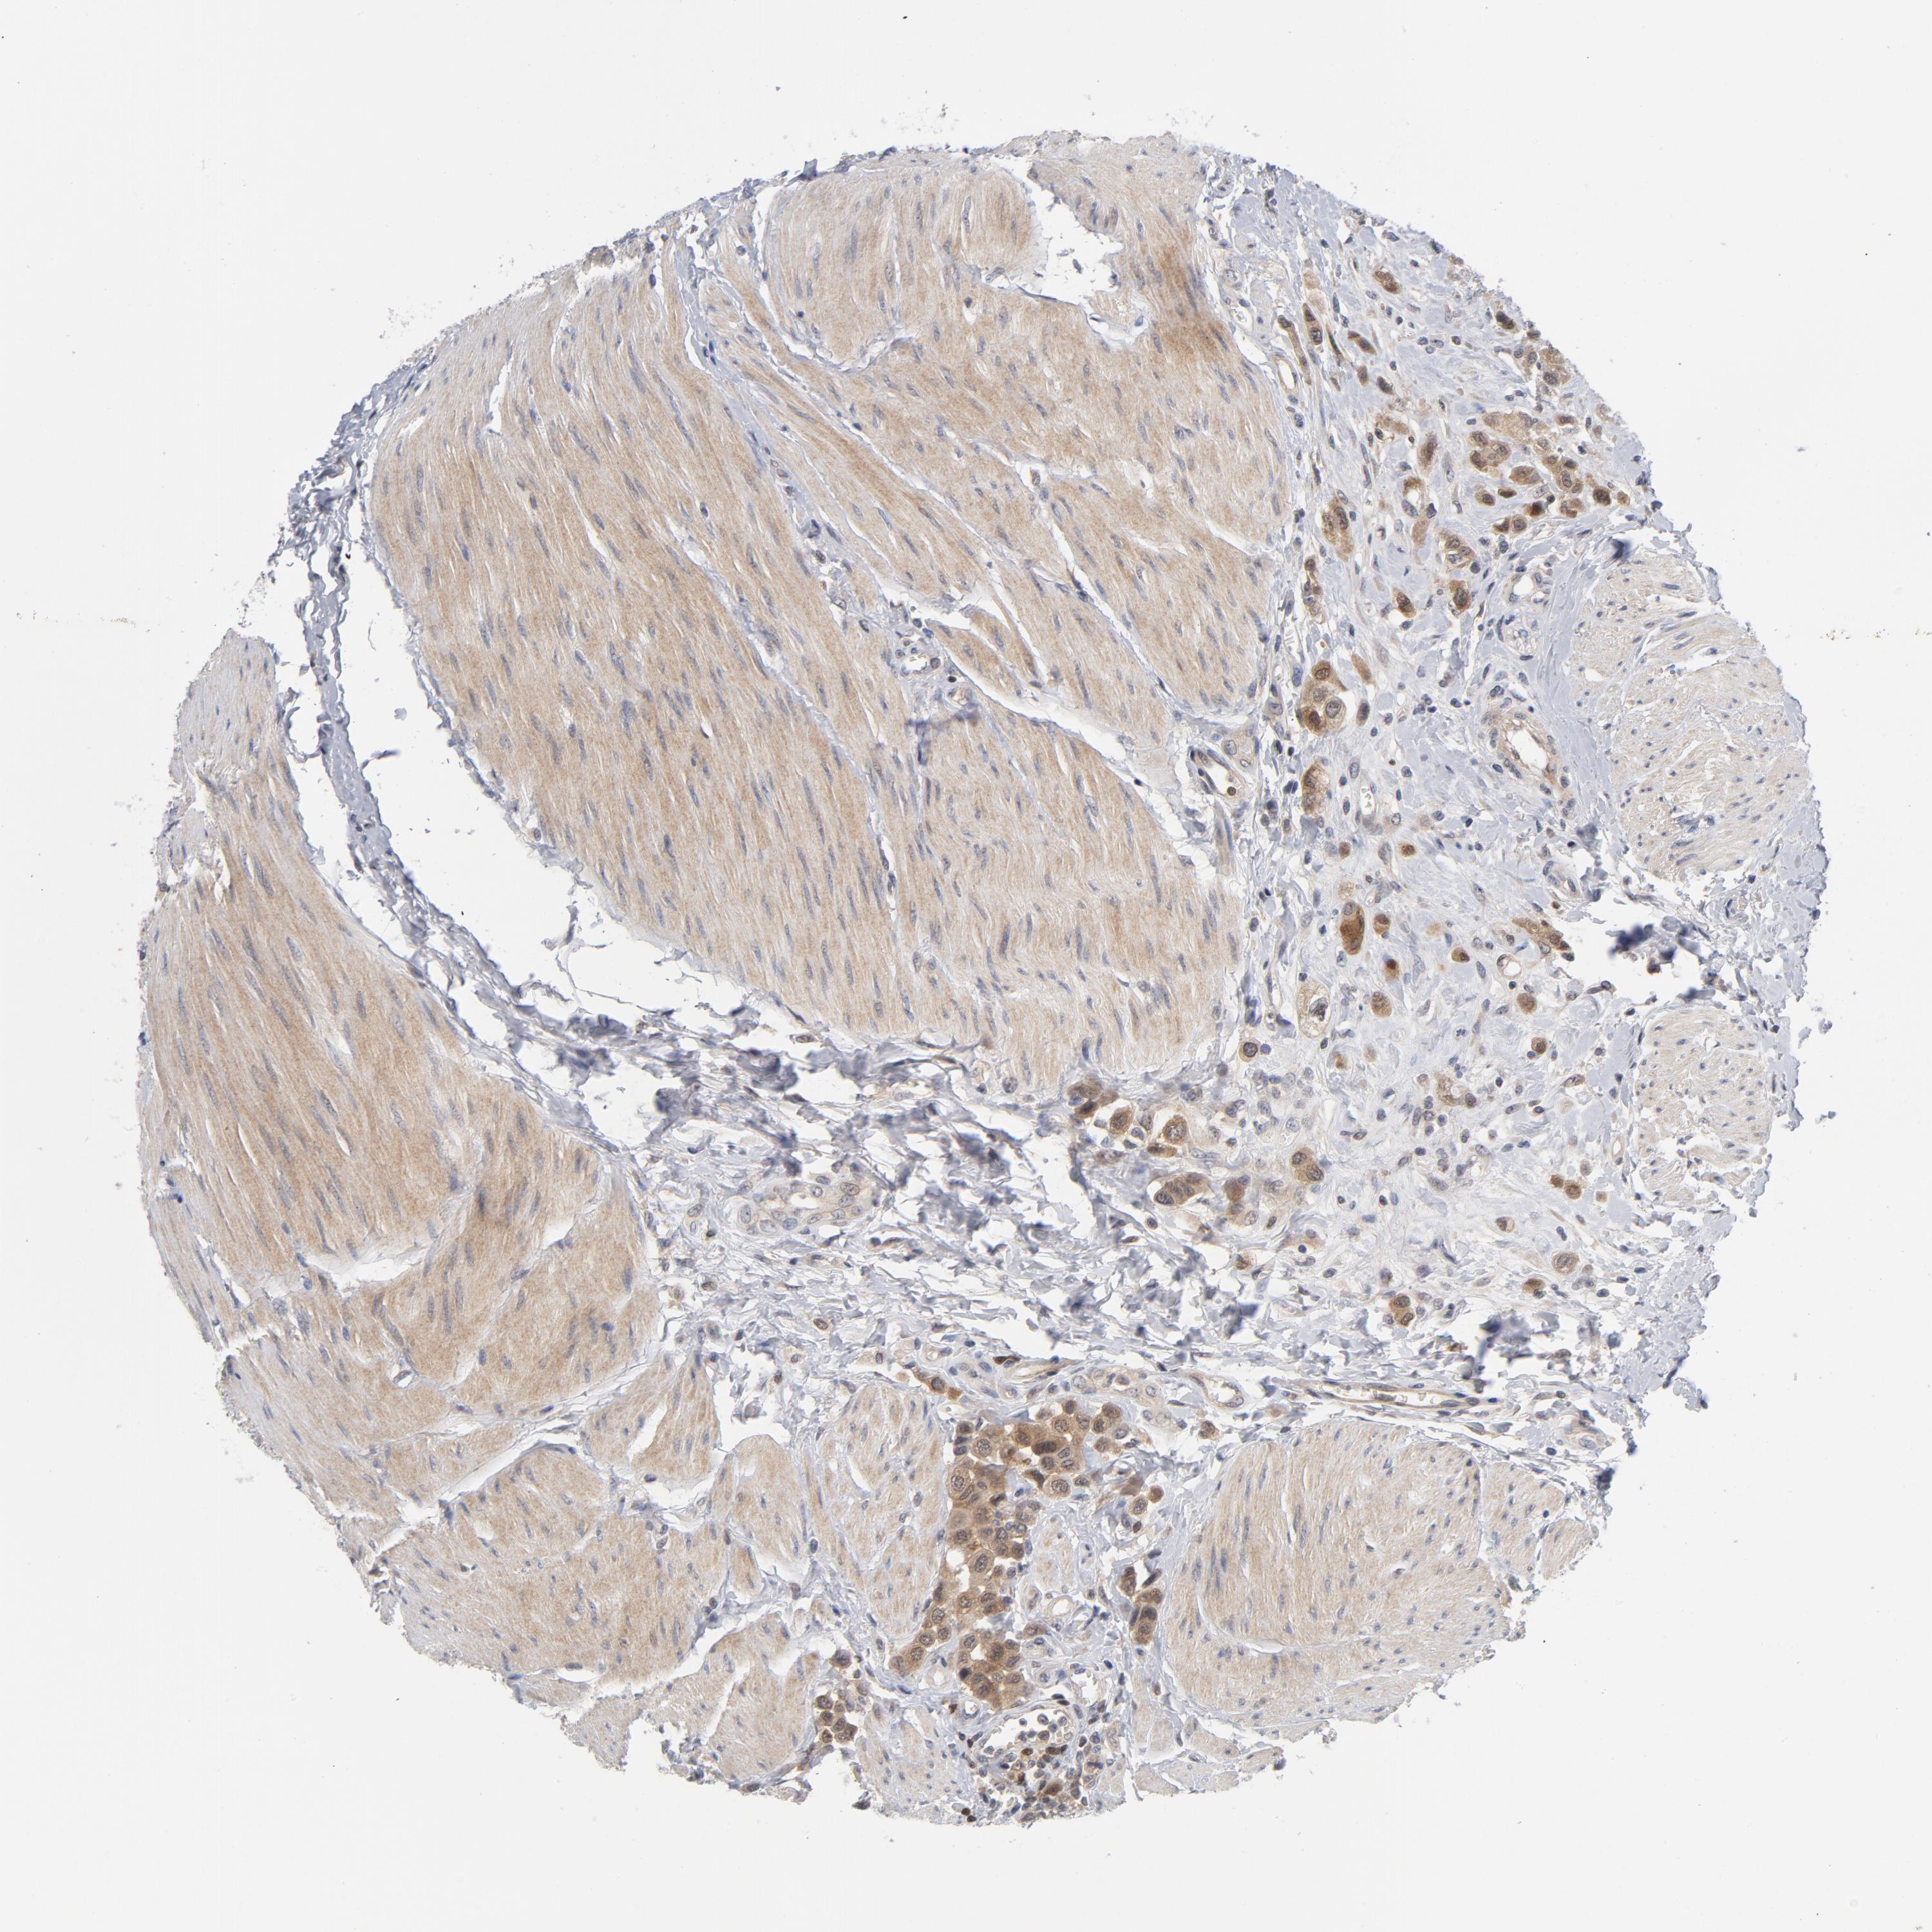

UROTHELIAL CANCER - Protein expressioni

A mouse-over function shows sample information and annotation data. Click on an image to view it in a full screen mode. Samples can be filtered based on level of antibody staining by selecting one or several of the following categories: high, medium, low and not detected. The assay and annotation is described here.

Note that samples used for immunohistochemistry by the Human Protein Atlas do not correspond to samples in the TCGA dataset.

Antibody stainingi

Antibody staining in the annotated cell types in the current human tissue is reported as not detected, low, medium, or high, based on conventional immunohistochemistry profiling in selected tissues. This score is based on the combination of the staining intensity and fraction of stained cells.

Each image is clickable and will lead to virtual microscopy that enables deeper exploration of all samples and also displays staining intensity scores, fraction scores and subcellular localization as well as patient and tissue information for each sample.

Antibody HPA071341

Antibody CAB004602

Staining

High

Medium

Low

Not detected

Intensity

Strong

Moderate

Weak

Negative

Quantity

>75%

75%-25%

<25%

None

Location

Nuclear

Cytoplasmic/membranous

Cytoplasmic/membranous,nuclear

Urothelial carcinoma, High grade

Urothelial carcinoma, NOS

Urothelial carcinoma, Low grade